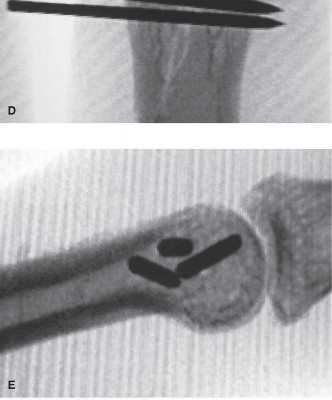

The correct answer is (E). This is an unstable injury as evidenced by the patient’s description of the deformity at the time of injury and by the radiographs seen in the office. The fracture is displaced and is an intra-articular fracture. There is an articular stepoff. Furthermore, it is an oblique fracture. All of these features indicate that this is an unstable injury, and treatment by closed means is unlikely to be successful. In fractures that are completely nondisplaced, closed nonoperative

treatment remains an option. However, in this instance where there is articular stepoff and displacement has occurred, it is vital to restore the length of the fragment, and more critically restore articular congruity especially in this young person. Closed reduction and percutaneous fixation as shown in the postoperative radiographs can be effective if perfect reduction of the joint is achieved (Fig. 4–10C to E). Failure to achieve perfect joint reduction by closed means necessitates an open reduction and treatment with either pins or screws.

Figure 4–10 C–E